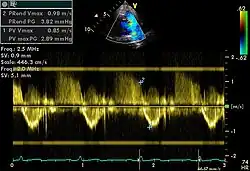

Spectral doppler

Spectral doppler through pulmonary vein

Spectral doppler is presented similarly to M-mode in which the doppler information is plotted as a spectrogram. This can be both "continuous" and "pulse" wave where the former shows the spectrum along a specific line and the latter shows within a small window along that line. Continuous wave is better at showing maximal velocities and pulse wave is better for showing flow through a small volume.

Spectral doppler is often used for quantification of flow. For example, the aortic valve area can be estimated using the continuity equation by measuring the velocity time integral (VTI) of the aortic valve & LV outflow tract; the VTI is calculated by tracing the flow on the spectral doppler curve. Spectral doppler is also useful for calculating the maximum flow and mean flow through a valve (used to grade valve stenosis).